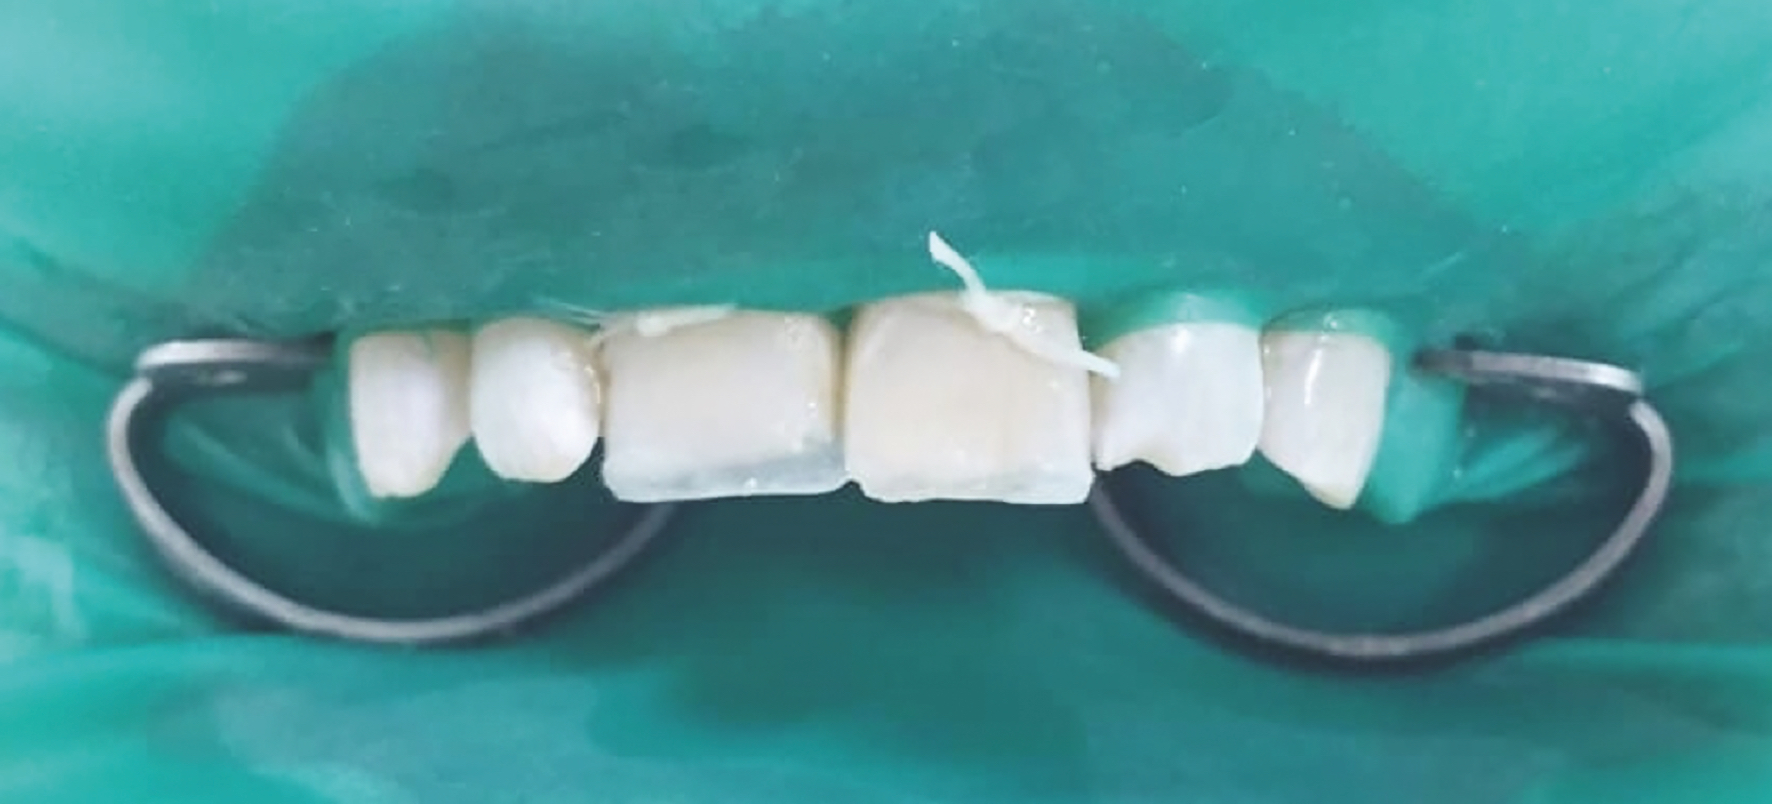

Figure 4

Figure 2 :  Vue du champ opératoire posé selon « la digue du sourire ». Création d’un mur palatin à l’aide d’une clé en silicone, reproduisant une coque amélaire.